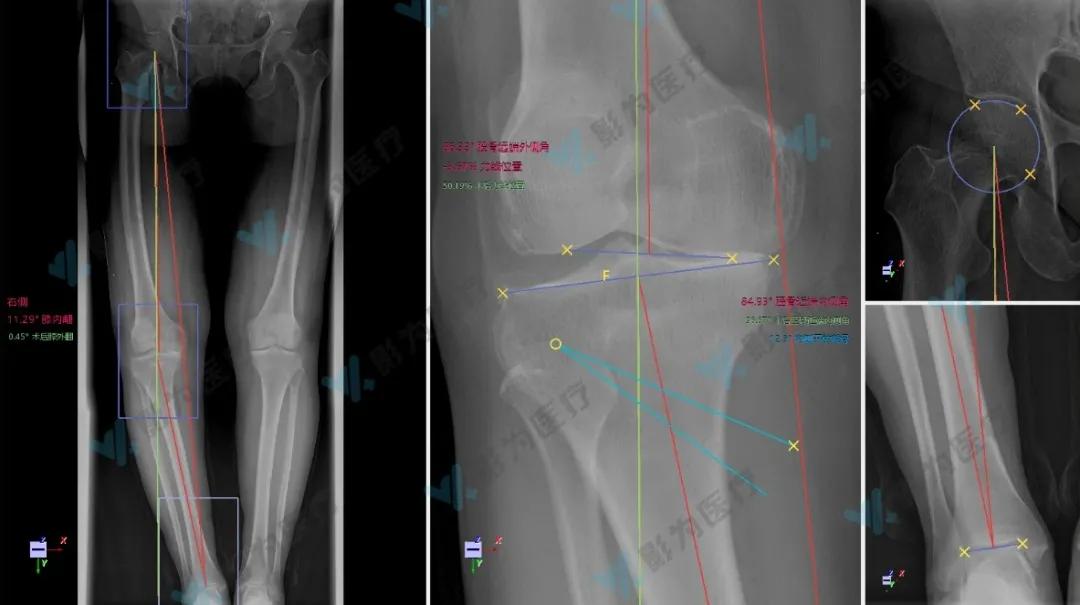

叶女士今年53岁,右膝疼痛多年,诊断为右膝关节骨性关节炎。检查结果显示,患者膝内翻角度为11.29,符合HTO最佳适应症。考虑到患者较为年轻,活动量大,医生团队决定遵循膝关节炎阶梯性治疗的理念,为其实施数字化HTO保膝手术,利用PSI辅助术中精准截骨。

影为医疗工程师利用自主研发的HTO专科手术规划软件,根据患者的X光片和CT数据,二三维联合规划得到负重位目标力线及撑开角度。在与符主任团队沟通确定规划信息并进行调整后,参数化截骨导板及量块一键生成。

患者下肢全长片的测量和规划

胫骨前后视图

上升截骨面到胫骨平台距离约40mm

胫骨内侧视图

上升截骨面切口到前方胫骨结节距离约10mm

拟撑开高度及量块放置位置